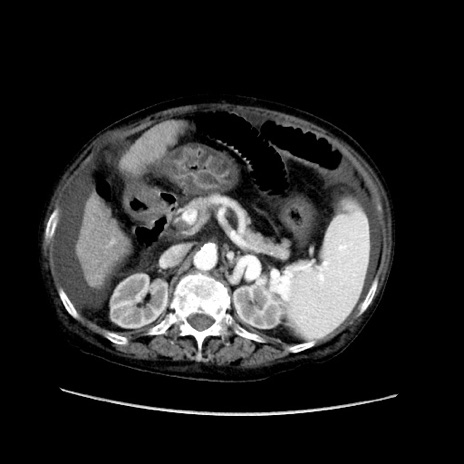

症例31(横断像)

【症例】80歳代 女性

【主訴】腹部膨満感

【現病歴】他院にて肝硬変にてフォロー中。1週間前から便秘、腹部膨満感、臍部腫瘤あり受診となる。

【既往歴】肝硬変

【身体所見】腹部膨隆あり、皮膚変化なし、疼痛なし。

【データ】WBC 4600、CRP 0.25